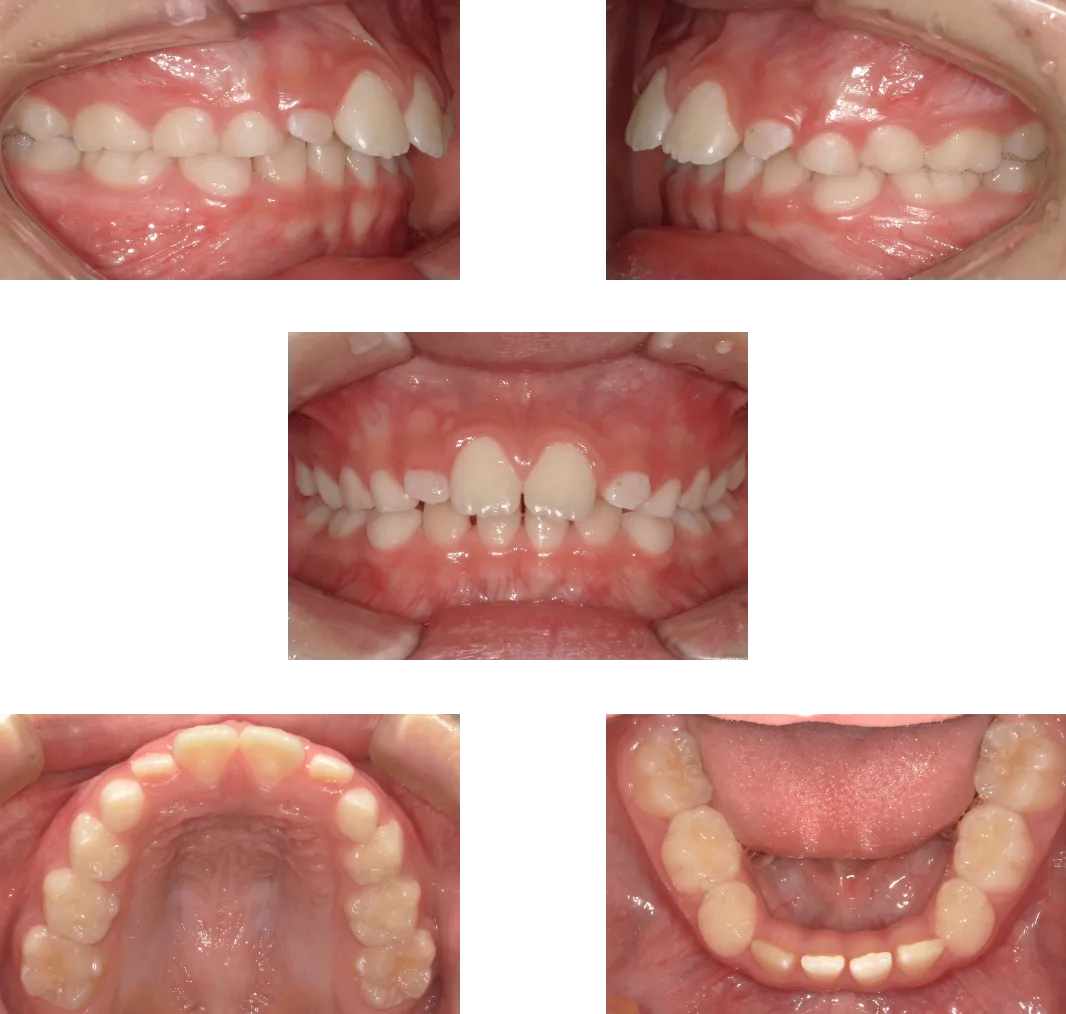

上顎前突 -15歳-

• Before

• After

診断

上顎の前歯唇側傾斜

治療期間

1年6ヶ月+保定期間2年

料金

950,000円

抜歯

なし

リスク

痛み、軽度の歯根吸収、術後の変化